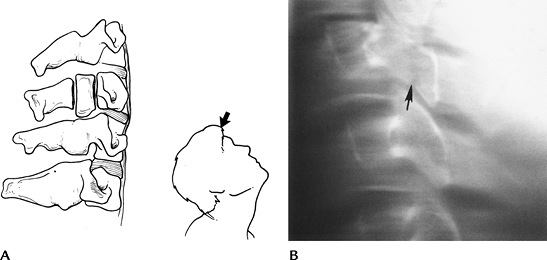

FIGURE 3-3 Disruptive hyperextension injuries. (A) Disruptive hyperextension injury with anterior distraction. The cord may be compressed. (B) Lateral radiograph shows anterior disc space widening and vertebral chip fracture (arrow).

FIGURE 3-4 Compressive hyperextension injuries. (A) Mechanism resulting in posterior compression and less anterior distraction. (B) Lateral radiograph demonstrating a vertical posterior arch fracture (arrow).